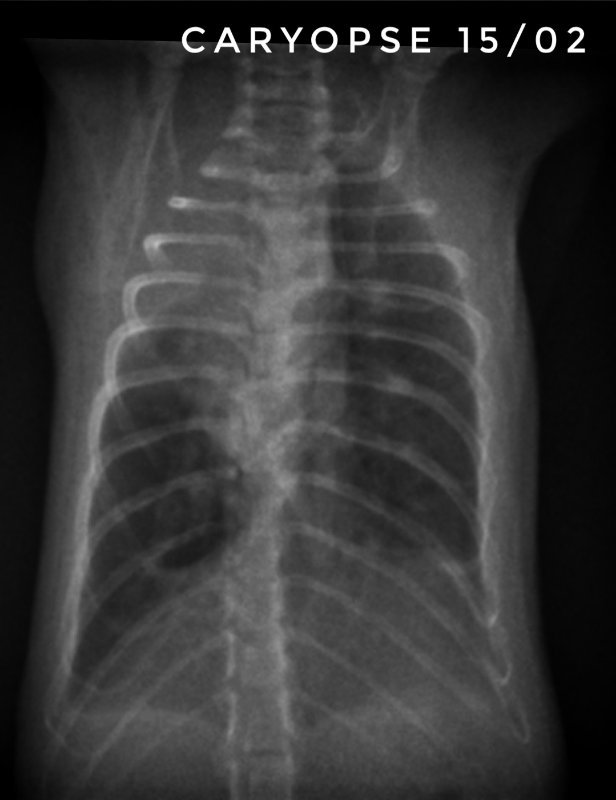

Toujours pour ceux que ça intéresse, les dernières  radios et le suivi du poids (Pyridion a commencé à perdre du poids le 04 mars, traitement changé le 08)

Et Caryopse, mon petit nain (180g) va physiquement pas trop mal, c'est à dire qu'il respire vite mais pas pire quoi... par contre ses radios sont... bref, le veto ne s'y attendait pas du tout lui non plus... en gros, petit mieux là où il était touché avant mais dégradation asur le reste du poumon...

Bon, du coup, les radios montrent que ça a empiré aussi chez Caryopse... On va donc tester le chloramphenicol, par un énorme coup de chance je peux traiter Caryopse avec (c'est un médicament interdit en France)... C'est un peu le traitement de la dernière chance. Pour lui, pas d'intérêt de faire d'autres analyses sur Pyridion (en dehors de dilapider mon argent) on sait déjà ce qu'ils ont, il faut juste réussir à trouver un traitement qui agisse...